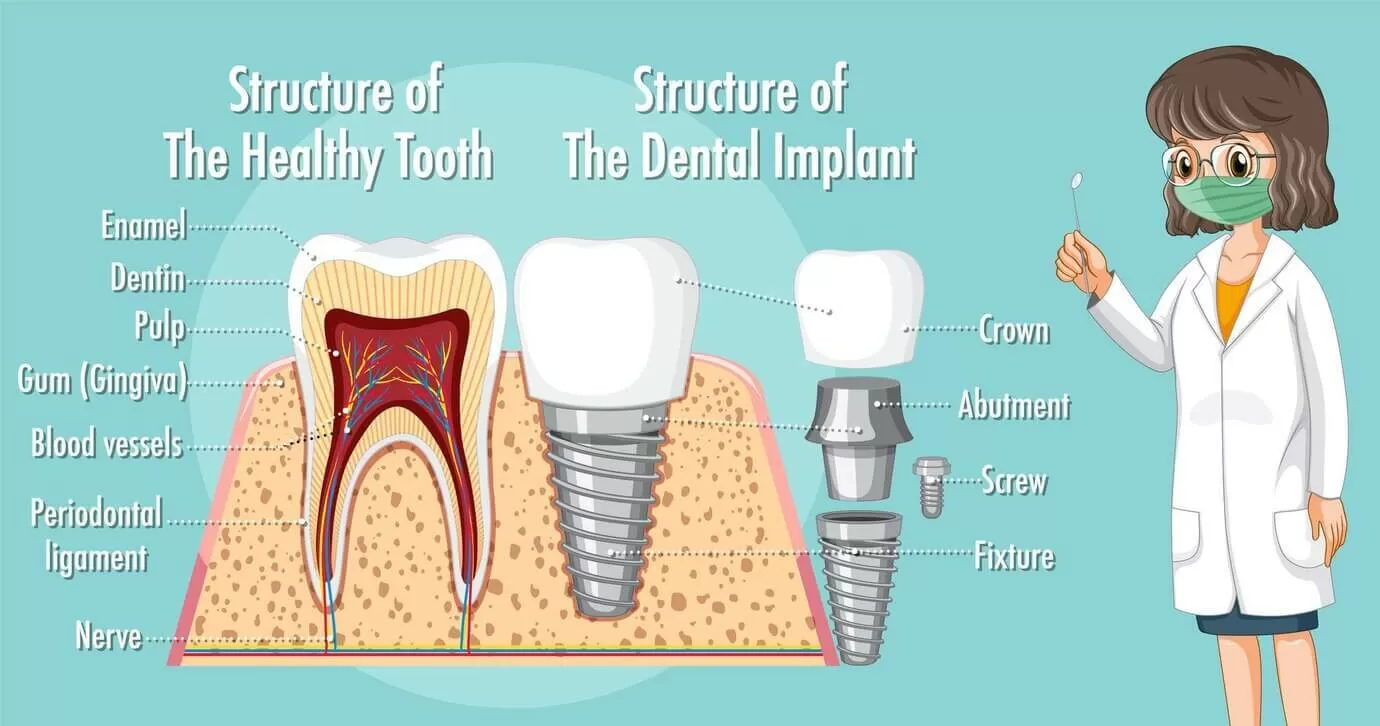

Имплант — винт из титанового сплава, который выступает в качестве искусственного корня. Как правило, он состоит из трех элементов:

- корневая часть, которую вживляют в челюстную кость;

- абатмент — служит опорой для мостовидного ортопедического протеза или коронки;

- коронка, имитирующая натуральный зуб.